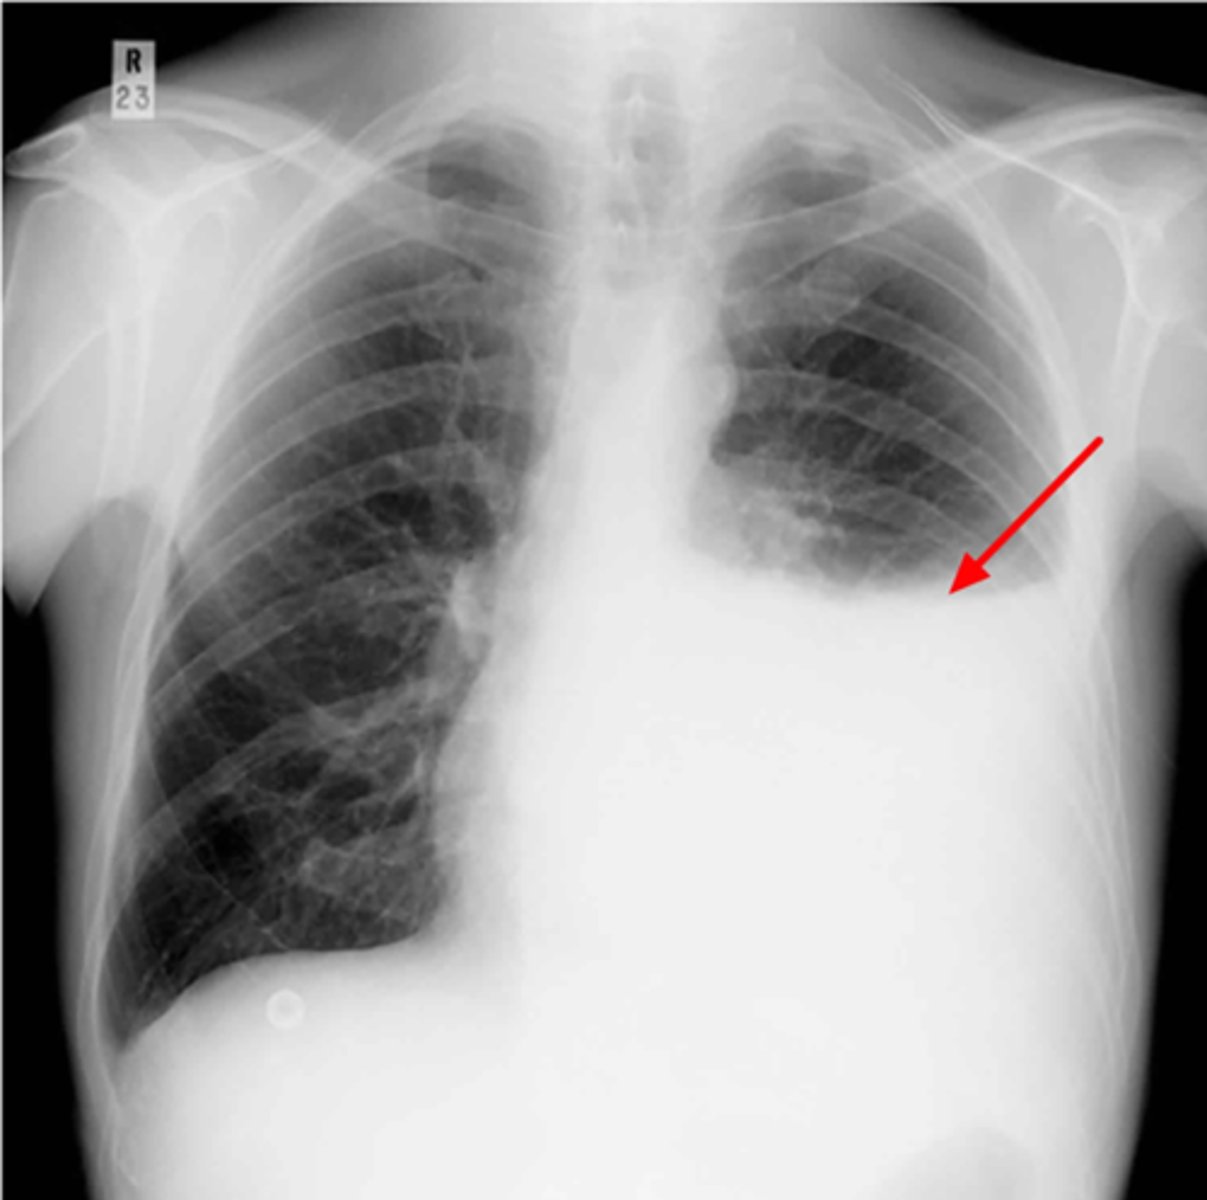

Is this patient rotated?

Yes

Is the Cardiac/Thoracic ratio normal?

Possible CHF (presence of Kerley B lines)

What does the chest film show?